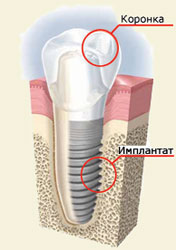

Протезирование зубов в Воронеже Протезирование зубов — один из методов реанимации зубного ряда. Протезирование нужно не только для того, чтобы ваша улыбка вновь стала эстетичной, но и для того, чтобы избежать дефектов дикции или ненужного смещения оставшихся зубов. В стоматологии «32 Плюс» изготавливаются протезы съёмного и несъемного типа из самых качественных материалов, при этом учитываются все физиологические особенности и требования пациента. Мы осуществляются различные способы протезирования верхней и нижней челюсти, полностью или частично восстанавливая зубной ряд. Специалисты с многолетним опытом, лучшие материалы и технологии — залог эффективной работы и качественного результата. Имплантация зубов в Воронеже Имплантация — ещё один метод восстановления зубного ряда, считающийся наиболее эффективным. Имплантат - это титановый сплав, вживляемый в костную ткань и выполняющий роль корня зуба. Внешне похож на металлический штифт. Зубные техники клиники «32 Плюс» обладают уникальными профессиональными навыками и изготавливают имплантаты исключительно из высококачественных материалов. Процедура имплантации зубов обладает многочисленными особенностями и преимуществами, о которых расскажут вам наши специалисты на консультации. Стоматология «32 Плюс» - гарантия безупречной улыбки Кроме стандартных стоматологических услуг в клинике «32 Плюс» проводятся процедуры, направленные на улучшение гигиены полости рта. Мы не используются агрессивные реактивы при отбеливании, поэтому гарантируем белизну и блеск ваших зубов с сохранением их прочности и целостности. Для безупречной стерилизации всех инструментов, приборов и помещений клиники используется система изоляции «Раббердам». Наибольшую эффективность лечения зубов обеспечивает совместная работа стоматологов с ассистентами в «четыре руки». Мы непрерывно работаем над совершенствованием оказываемых нами стоматологических услуг, не только используя различные технологические инновации, но и разрабатывая дополнительные методики лечения. Также наши врачи регулярно обновляют и дополняют свои профессиональные знания: посещают курсы по повышению квалификации, изучают труды зарубежных и отечественных коллег, проходят специальное обучение. Специалисты клиники «32 Плюс» проявляют чуткость и внимательность к каждому пациенту, подбирая каждому оптимально подходящую индивидуальную программу лечения. Стоматологическая клиника «32 Плюс» - с нами Ваша улыбка станет «голливудской»! |